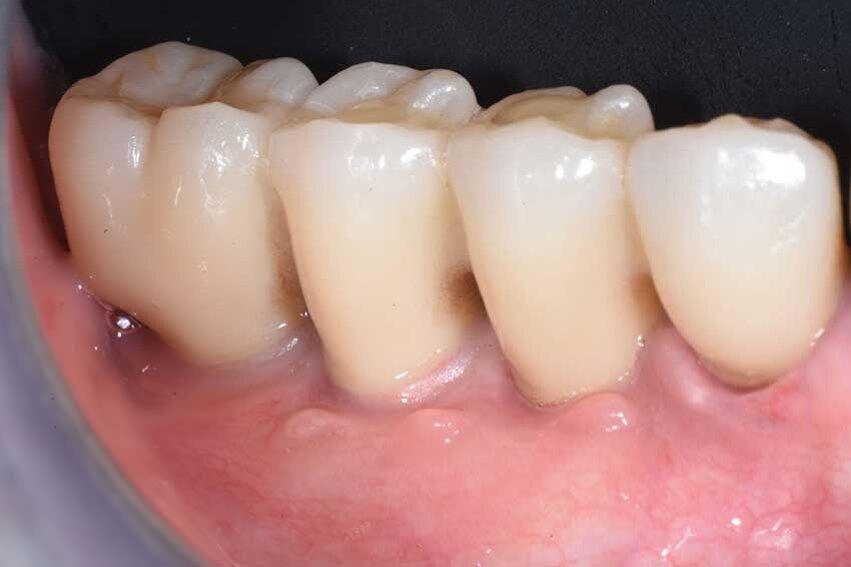

Una paziente di 65 anni si presentò alla nostra attenzione, riferita dal dentista curante, per risolvere il suo edentulismo posteriore bilaterale. L’anamnesi medica era negativa, mentre la paziente riferiva di aver perduto i denti diatorici come conseguenza di fratture susseguenti ad una vecchia protesizzazione (Fig. 1a).

Circa otto settimane più tardi si è potuto notare l’integrazione degli innesti (osseo e tessuto molle) e la notevole differenza nel volume vestibolare della cresta (Fig. 13). Tre mesi dopo la scopertura degli impianti e dopo che i tessuti erano completamente guariti venivano rilevate le impronte e finalizzate le corone in zirconia (Fig. 14). La rx rilevata a sei mesi dalla finalizzazione protesica (Fig. 15) dimostra la stabilità del complesso implanto protesico e la completa ricostruzione del difetto osseo circostante agli impianti.

La figura 16 evidenzia, se paragonata a quella iniziale, come la zona edentula inizialmente concava, presenti ora una forma convessa a protezione del restauro protesico.

Fig. 14 - Le corone definitive in posizione.